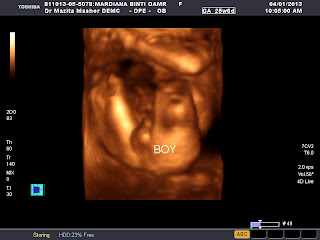

Inila gambar 3D scan yang di ambil pada 4/1/2013. When the doc scan baby, my due date was 13th April, and Doc cakap it seems like besar seminggu so mummy put 7th April as a dateline. Senang kan. Susahnya nak ambil gambar muka dia, asyik tutup dengan tangan.

The explanation was so good. Doc explain every line, everything bout the the baby. InsyaAllah dengan izin Nya, baby ni sihat dan sempurna hendaknya. Amin.

Baby tak malu-malu nak menunjukkan gender secara terang - terangan.

Tengokla tu dia show off his bebird. Hahahahahahhaha..